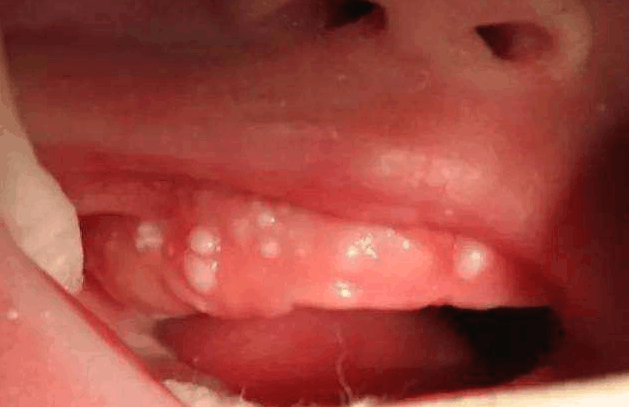

前不久,小丽生了一个很可爱的宝宝。在坐月子期间,小丽是什么都不用干,每天就只看着宝宝。这天,小丽在逗宝宝笑的时候,发现宝宝口腔上面的硬腭上有黄白色小颗粒。小丽以为这是宝宝上火了留下的水泡,害怕影响宝宝吃奶。于是就动手给宝宝挤破了。

过了一天,小丽发现宝宝口腔里出现了炎症,还想自己昨天的判断很正确,宝宝确实是上火了。又过了几天,宝宝嘴里的炎症并没有好转,并且是更严重了,这让小丽很害怕,于是就带着宝宝去了医院。医生看到宝宝后,大骂小丽愚蠢。医生告诉小丽,那是宝宝的马牙,宝宝的马牙是挑不得的。

其实,马牙并不是牙,在宝宝奶过程中牙床和乳头摩擦,经过一段时间后“马牙”便会自行脱落。所以,各位妈妈们,不要挑破孩子马牙,如果孩子炎症严重的话,是会引起孩子败血症的,到时候,后悔可是来不及了。